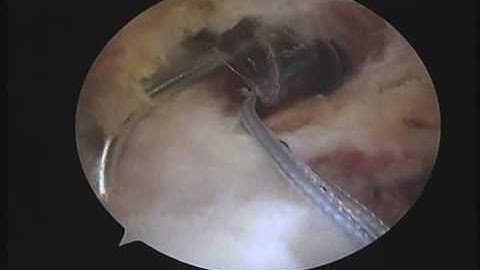

Partial thickness rotator cuff repair using a bio-composite scaffold